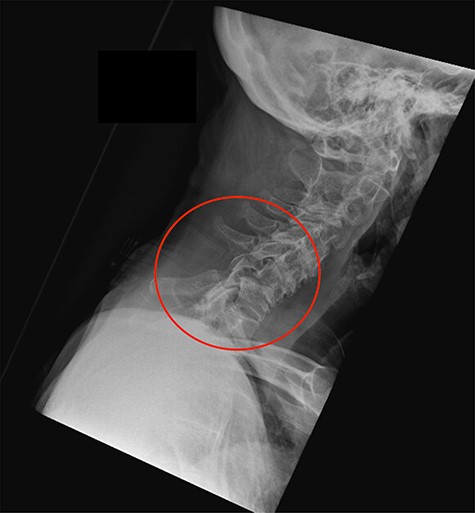

The left shoulder radiograph showed no abnormality. The sagittal images of the cervical spine CT scan are shown in Figs 1 and 2a and b. Figure 1 is the mid-sagittal slice of the CT scan at presentation and shows no obvious malalignment.

Midline sagittal CT scan of the cervical at the time of first presentation.